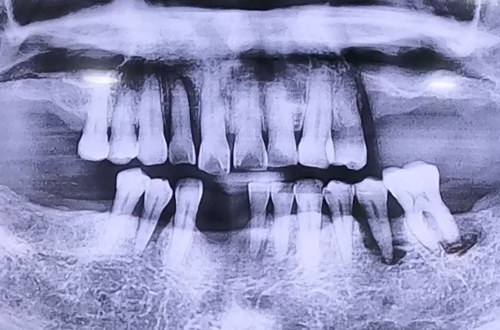

BEFORE

잇몸의 문제로 어금니 등 여러 치아를 뺀 상태로 내원해 주셨던 환자분으로,

윗니, 아랫니의 앞니 임플란트까지 전반적인 임플란트 치료를 계획하고 진행 중인 환자분입니다.

이를 빼고 시간이 흐르면서 좌우 위아래 모두 어금니들의 잇몸뼈가 많이 약해져 있어

잇몸뼈를 튼튼하게 회복시키고, 주위 신경 등에 주의하며 안전하게 임플란트 진행을 계획하였습니다.

특히 앞니는 엑스레이로 보았을 때 잇몸뼈가 상당히 얇아진 상태였기 때문에 임플란트 수술을

진행하면서 필요 시 뼈이식을 진행하기로 하여, 확인 후 뼈이식 임플란트를 시행한 케이스입니다.